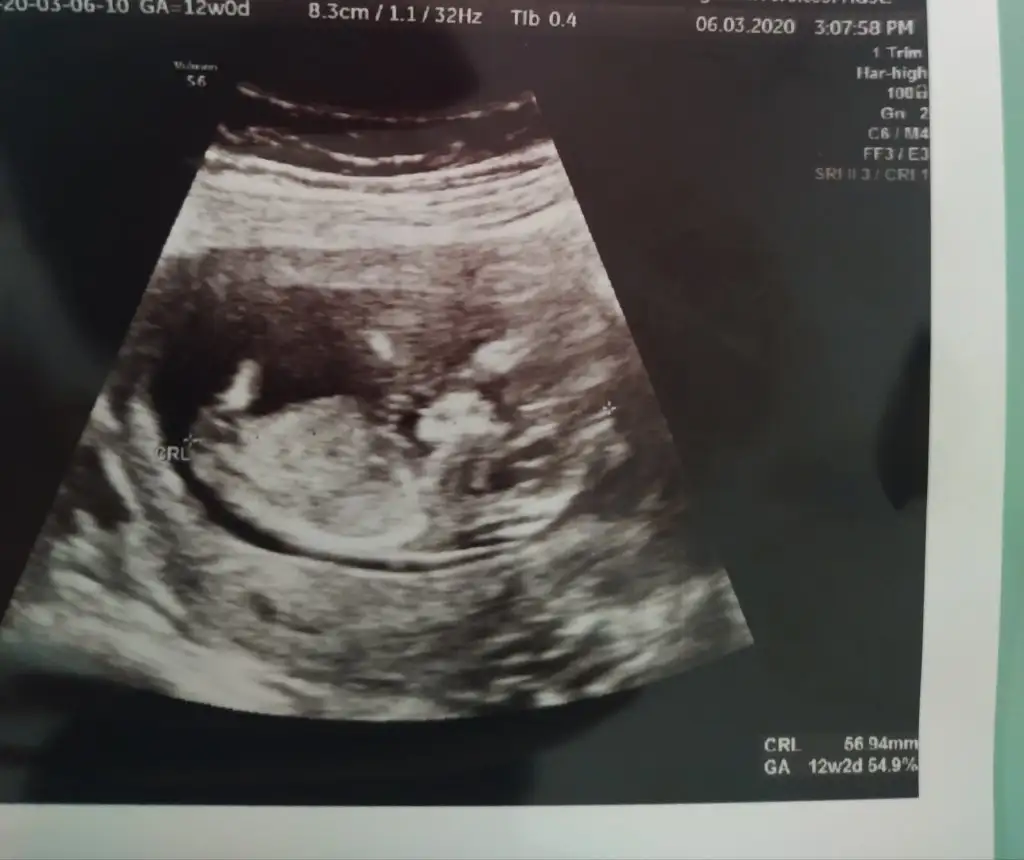

13 haftalikken bir doktor kız dedi 1 hafta sonra başka bir doktor erkek dedi 3 hafta sonra kız diyen doktor yine kız dedi ama hiçbiri net konuşmuyorHayırlısı çok net değil usg bakalım kızmı erkekmi şimdi kaç haftalık hamilesiniz dr ne zaman kız yada erkek dedi devaml gittiğiniz drmu kız yada erkek dedi

Bencede kız 2 defa kız demiş aynı dr13 haftalikken bir doktor kız dedi 1 hafta sonra başka bir doktor erkek dedi 3 hafta sonra kız diyen doktor yine kız dedi ama hiçbiri net konuşmuyor

Sanki kız gibi ama emin değilim nubu karanlık kalmış 12 yada 13 haftada paylaşın emin olmak istiyorum